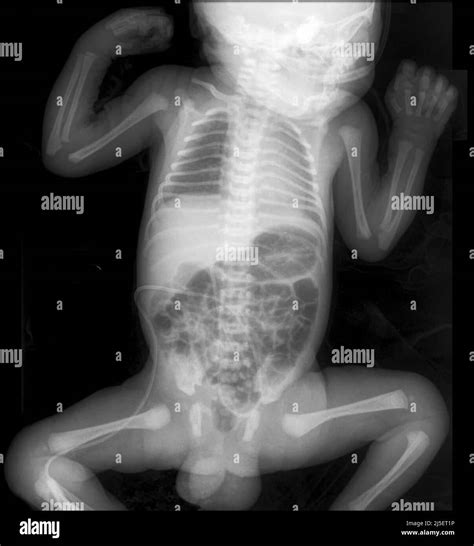

Infant X-ray imaging involves the use of low-dose radiation to produce images of the internal body structures. This technique is particularly useful for diagnosing conditions such as fractures, pneumonia, and congenital anomalies. The process is quick and relatively painless, making it suitable for infants who may be too young to cooperate with more complex diagnostic procedures.

• Assessment of Congenital Anomalies: X-rays can help identify congenital anomalies, such as heart defects or skeletal abnormalities, which may require immediate medical attention.

Congenital Anomalies X-rays can reveal congenital anomalies, such as heart defects or skeletal abnormalities, which may require immediate medical attention.

Foreign Bodies X-rays can locate foreign bodies, such as swallowed objects or inhaled items, which may require removal.